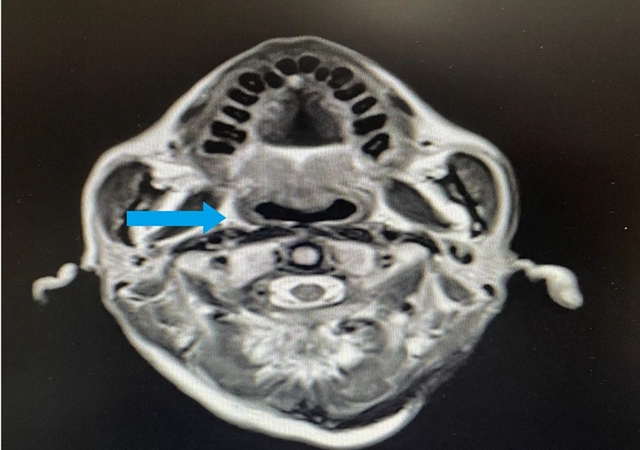

鼻咽部核磁共振:鼻咽部粘膜明显增厚(右侧为甚),鼻咽腔变窄,符合鼻咽癌变表现,双侧颈部多发淋巴结增大转移,右侧为多;

综合检查结果,西医诊断为:鼻咽部恶性肿瘤(分化型非角化性癌)侵及口咽、咽旁间隙伴咽后、颈部转移淋巴结;肺继发恶性肿瘤;中医诊断为鼻咽癌(痰瘀互结)。

治疗3月后,李大叔复查胸部CT与上次比较,肺部结节缩小,大小约1.6×1.3cm²;复查鼻咽部MRI提示:鼻咽部病灶明显缩小,右侧咽旁间隙肿大淋巴结未见显示,颈部双侧淋巴结数量减少、体积缩小。